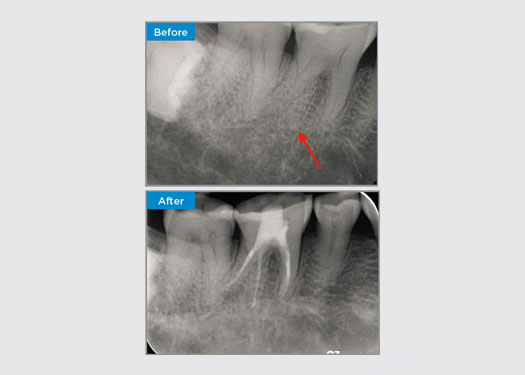

Casos clínicos